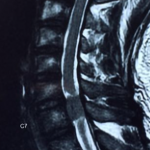

經詳細問症後,很明顯林生的問題已出現馬尾神經綜合症的病況.可能椎管內有腫瘤或腰椎嚴重椎間盤突出壓迫脊髓. 後立刻安排病人照全脊椎磁力共振,並2小時後立即幫病人看片, 果然發現病人頸椎6/7節椎管位置長了一個1.6cm腫瘤嚴重地壓著脊髓. 當日立即轉介至腦神經外科醫生,並安排當晚入院,第二日做割除頸椎管腫瘤手術. 病人術後,腳痛及痲痺,腳部乏力也徐之而改善.

頸椎6/7節椎管位置長了一個1.6cm腫瘤嚴重地壓著脊髓

頸椎6/7節椎管位置長了一個1.6cm腫瘤嚴重地壓著脊髓